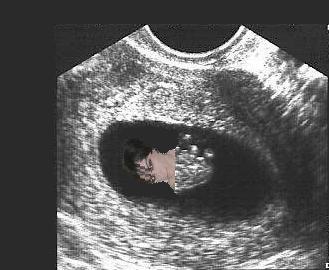

We had a little scare on Friday and I was given an early ultrasound. Fortunately, everything looked good. Baby measured just right for it's age (about 8wks) at 1.5cm and the little heart was beating along at a steady 145bpm (also very good). Everything else looked good as well. I thought I would include a picture for anyone interested.

baby2.jpg

baby2.jpg [ 19.12 KiB | Viewed 5179 times ]